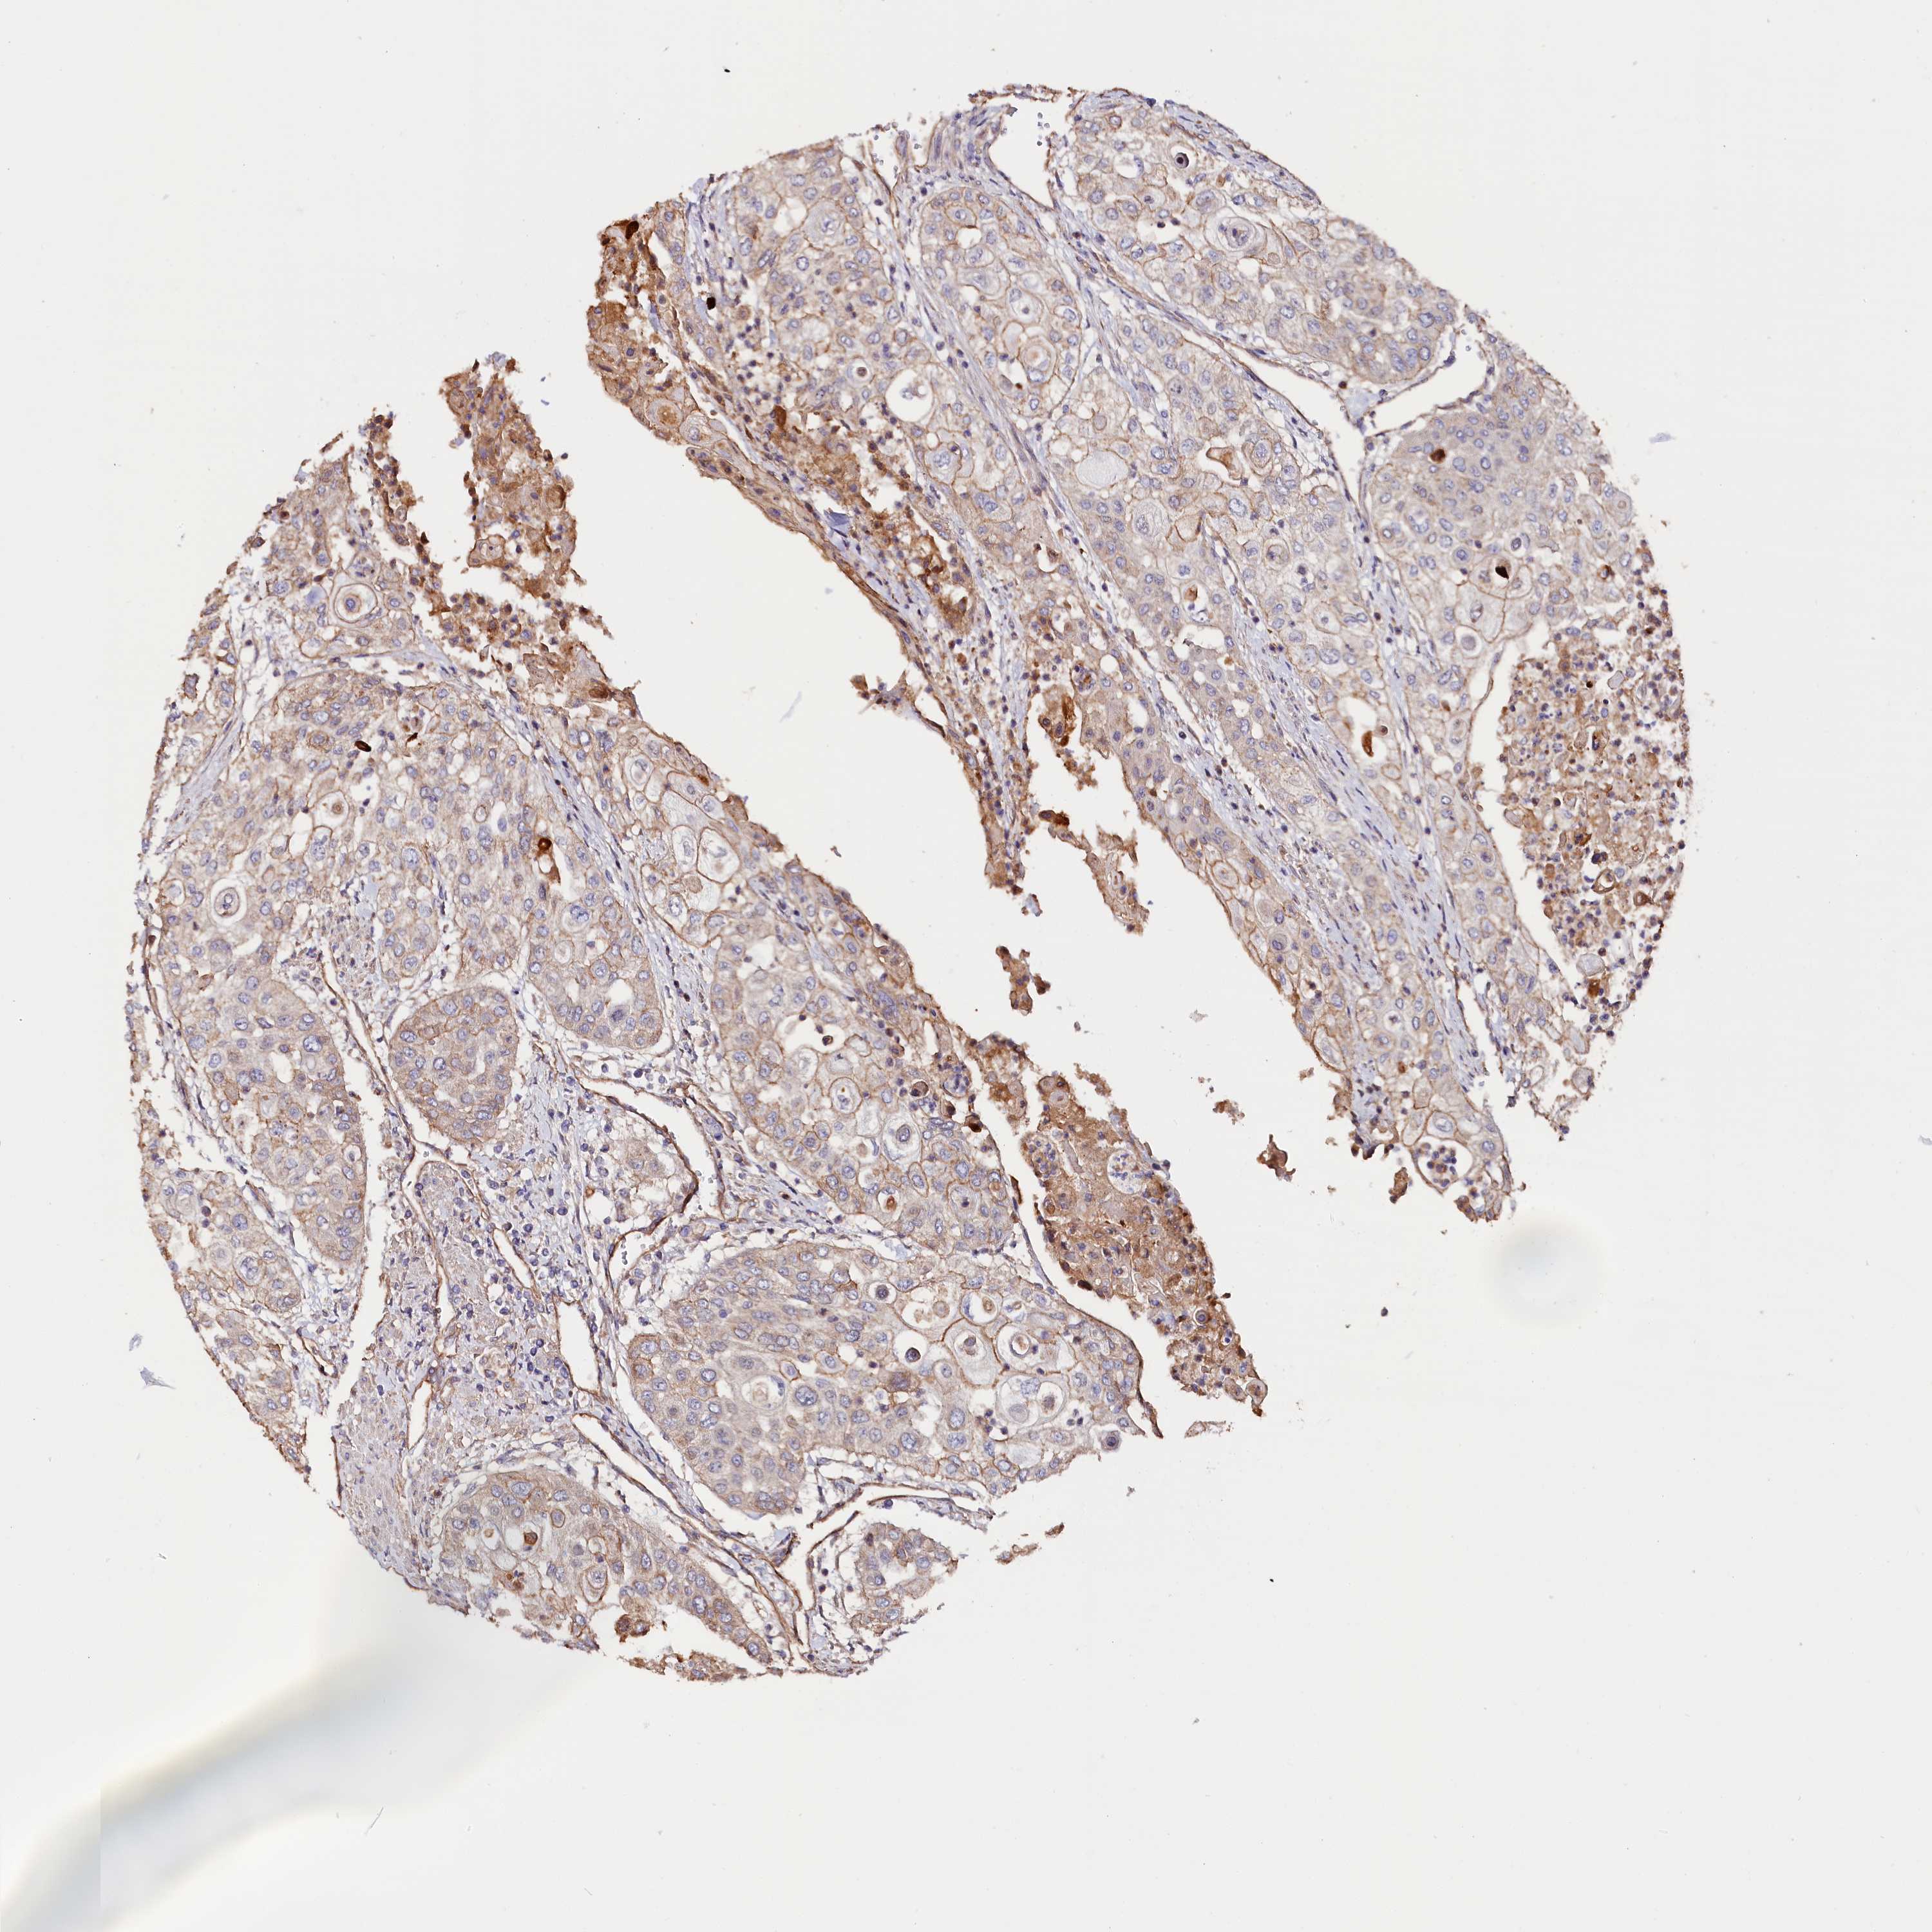

UROTHELIAL CANCER - Protein expressioni

A mouse-over function shows sample information and annotation data. Click on an image to view it in a full screen mode. Samples can be filtered based on level of antibody staining by selecting one or several of the following categories: high, medium, low and not detected. The assay and annotation is described here.

Note that samples used for immunohistochemistry by the Human Protein Atlas do not correspond to samples in the TCGA dataset.

Antibody stainingi

Antibody staining in the annotated cell types in the current human tissue is reported as not detected, low, medium, or high, based on conventional immunohistochemistry profiling in selected tissues. This score is based on the combination of the staining intensity and fraction of stained cells.

Each image is clickable and will lead to virtual microscopy that enables deeper exploration of all samples and also displays staining intensity scores, fraction scores and subcellular localization as well as patient and tissue information for each sample.

Antibody HPA041165

Antibody HPA041839

Urothelial carcinoma, High grade

Urothelial carcinoma, Low grade